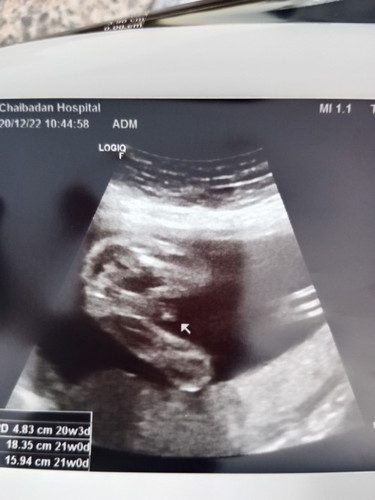

ช่วยดูเพศหน่อยคะ ช. หรือ ญ.

แม่ๆท่านไหนดูออกบ้างคะ

ชายจ้าเเม่ ของเราก้อเเบบนี้ได้ลูกชายจ้า

แบบนี้ ชาย นะคะแม่❤️❤️

ชายค่ะ เด่มาขนาดนั้น

ผู้ชายค่ะแม่

เราว่าชายค่ะ